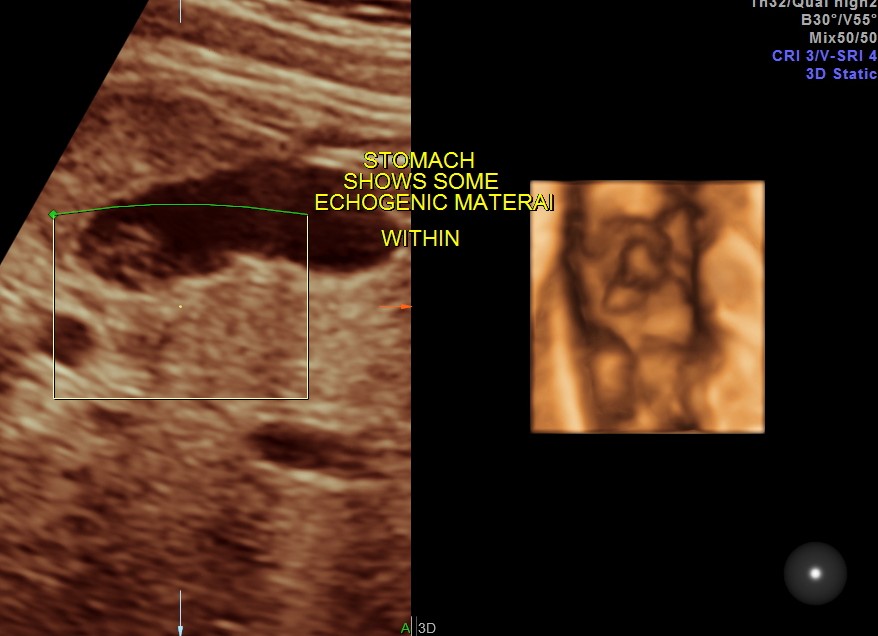

Echogenic material is seen within the stomach.

The following are 3 d images , which prove that this was not an artefact.